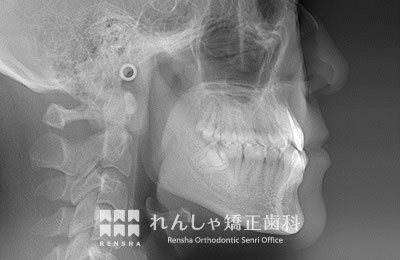

大人

軽度の上顎前突であれば、上奥歯の後方移動で前歯の前突を改善することもありますが、上顎前突は叢生の問題も絡んでいることがほとんどで、永久歯の抜歯が必要になることがあります。また上奥歯の後方移動には矯正矯正用アンカースクリューの併用が効果的です。

治療前

| 主訴 | 出っ歯と前歯のがたつき |

|---|---|

| 診断名 | Angle Class II 上顎前突 |

| 初診時年齢 | 20歳7か月 |

| 装置名 | マルチブラケット装置 矯正用アンカースクリュー |

| 抜歯非抜歯 | 上下顎左右第二小臼歯の抜歯(合計4本) |

| 治療期間 | 3年2か月 |

| 費用の目安 | 約75万円+消費税(検査料金、都度の処置費用等も合わせた総額) |

| リスク副作用 | 歯の移動に伴う軽微な歯根吸収、歯槽骨吸収、歯肉退縮(本症例では軽度の歯肉退縮と歯根吸収を認めた)、矯正器具装着中のカリエスリスク増大(本症例では大臼歯にカリエスが発生し、その後う蝕処置)、上顎左側犬歯の失活 |